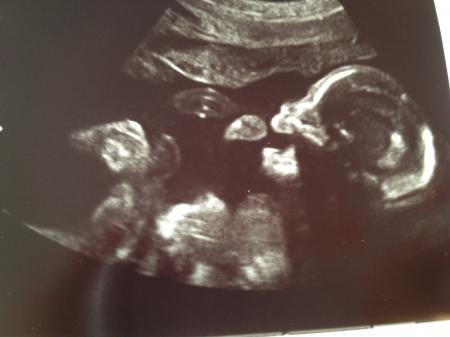

Morgen Bin wieder zurück vom Termin und noch immer ganz verliebt Der Kleine war wohl erst am schlafen und wurde dann vom Arzt "wachgerüttelt", hat sich prompt gedreht und angefangen zu zappeln und am Daumen zu lutschen. Voll süß Letztlich lag er gut und der Arzt konnte sich alles in Ruhe anschauen und vermessen. Herz, Lunge, Nieren, Plazenta, Blutfluss, Nabelschnur, Fruchtwasser, Gehirn usw. ist alles so wie es sein sollte und es gab keine Auffälligkeiten. Männe war auch dabei und ganz glücklich. Jetzt bin ich echt erleichtert und hoffe, dass die SS weiterhin so unbeschwert bleibt :-) Hab leider nur vergessen nach der Gesamtgröße zu fragen und muss mir das noch aus allen vermessenen Einzelgrößen zusammenrechnen... Hänge mal noch ein paar Bildchen ran. Leider hatte er auf den 3D-Bildern immer den Arm vorm Gesicht. Aber ich bekomm ja bei meiner Ärztin auch nochmal die Chance auf tolle 3D-Bilder. Ist mal wieder richtig lang geworden Liebe Grüße von der glücklichen Tina

Bild zu Zurück von der FD - Forum für August - Mamis

Toll, das Alles gut ist mit dem Kleinen ! Freut mich sehr für Dich! Wundervolle Bildchen hast Du da von Deinem Prinzen ... Auf dem 2. sieht er aus, als würde er lachen, echt sweet ! LG Mone